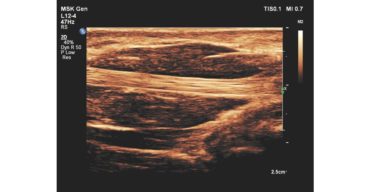

ecografo PHILIPS affiniti 30

La scelta di un nuovo sistema ecografico è tutta questione di equilibrio. Servono velocemente informazioni diagnostiche precise, un'interfaccia utente semplificata ma intuitiva e facilità di accesso alle funzioni cruciali, unitamente a un design ergonomico e alla tecnologia più recente.

Affiniti 30 rappresenta un’investimento intelligente in quanto risponde compiutamente alle sollecitazioni quotidiane legate alla produttività, alla qualità diagnostica e ai bassi costi di gestione.